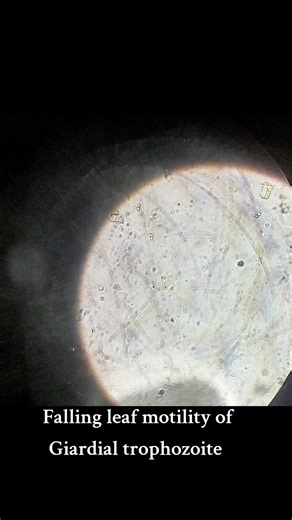

Sids - G.Lamblia Micrscopic

Fall Greenscreen - Giardia Lamblia

Giardia - Giardia Parasite

Motility - Giardia Lambdia

Motility - Giardia Lambia